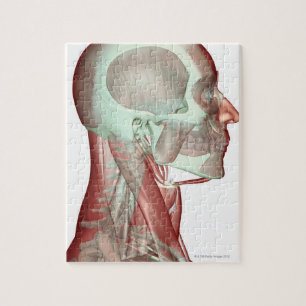

Impressão Em Tela Músculos da parte traseira e do pescoço

PreçoR$ 467,00

Produto oficialmente licenciado